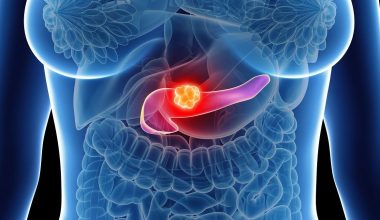

Όλοι μας γνωρίζουμε πως ο πόνος στις αρθρώσεις μπορεί να γίνει τόσο εξουθενωτικός ώστε να δυσκολεύει την εκτέλεση ακόμη και απλών καθημερινών εργασιών.

Οι αρθρώσεις του σώματος είναι μαλακοί ιστοί που επιτρέπουν την κίνηση και την ευελιξία.

Η κύρια αιτία του πόνου στις αρθρώσεις είναι η βλάβη στην εσωτερική επένδυση της άρθρωσης. Αυτό μπορεί να προκληθεί λόγω υπερβολικής χρήσης ή τραυματισμού.

Οι αρθρώσεις που επηρεάζονται συχνότερα είναι τα γόνατα, οι γοφοί, οι ώμοι και οι αγκώνες.

Οι πόνοι στις αρθρώσεις ξεκινούν συνήθως γύρω στα 40, αλλά μπορούν να εκδηλωθούν σε κάθε ηλικία.

Δοκιμάστε να αντιμετωπίσετε τους πόνους στις αρθρώσεις με φυσικές θεραπείες, όπως περιγράφονται στο βίντεο πoυ ακολουθεί: